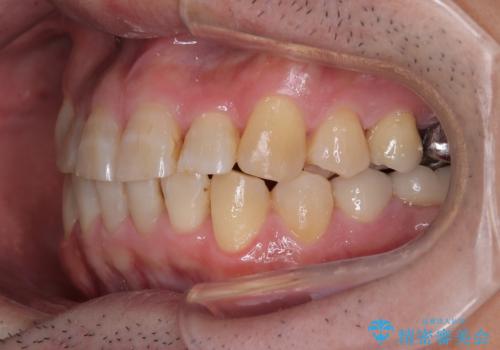

むし歯をきっかけに矯正治療を行うこととなりましたが、学生の頃から気になっていた歯列を改善することができ、患者様には大変満足していただけました。